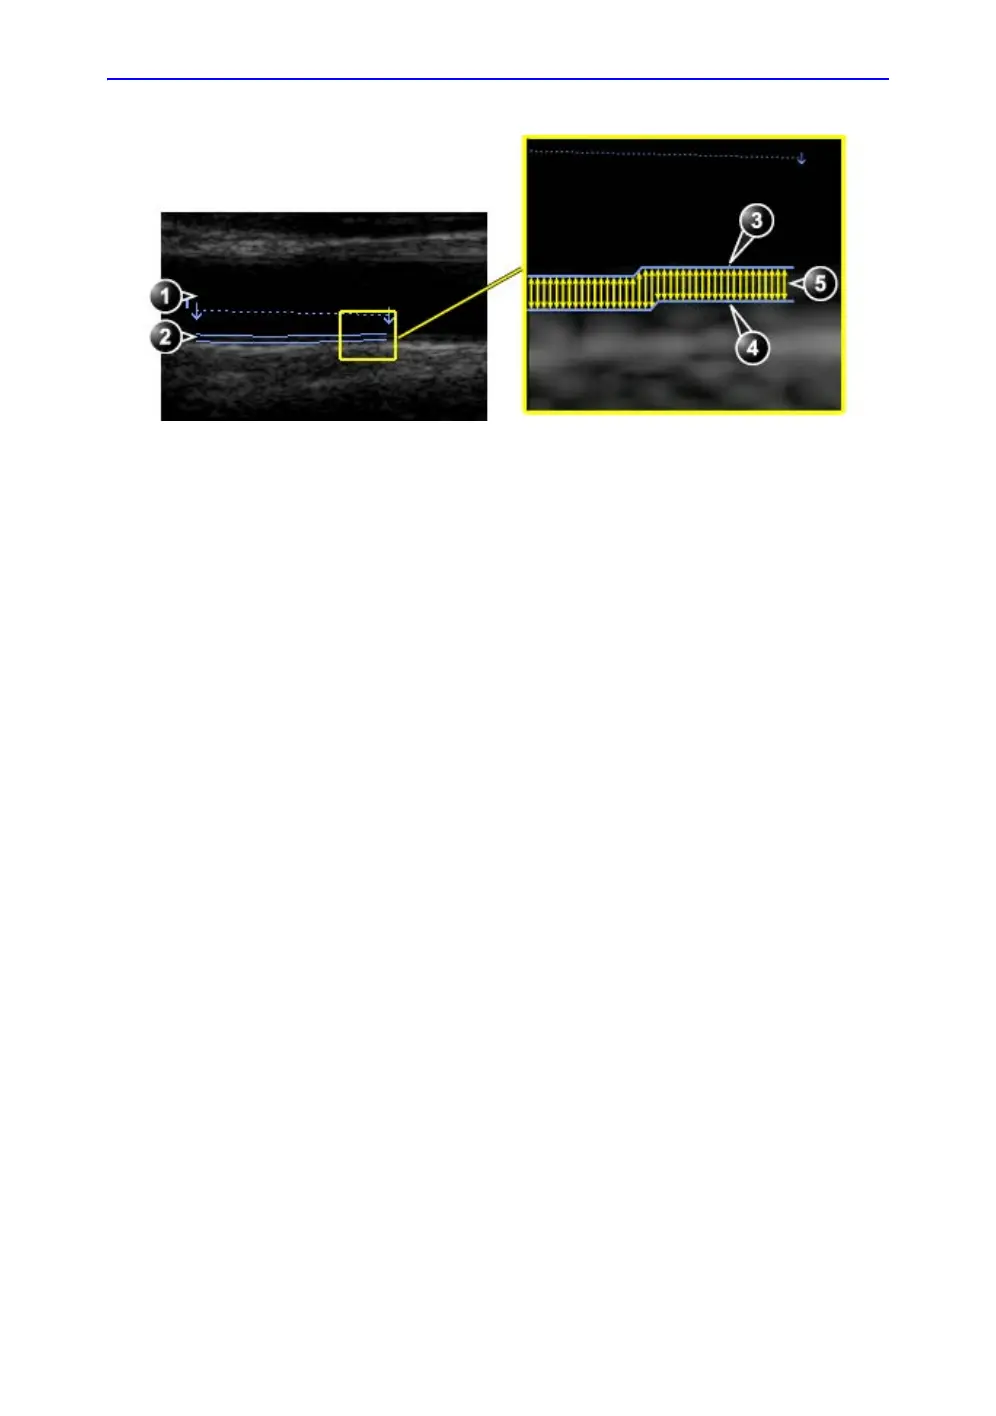

Figure 8-47. IMT measurement (Posterior wall)

1. Vessel lumen

2. Vessel wall

3. Lumen-Intima boundary

4. Media-Adventitia boundary

5. Multiple IMT measurements